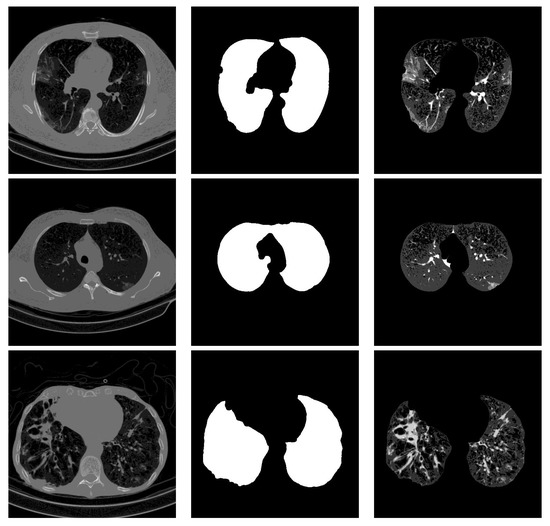

For lung segmentation, we used marker-based watershed segmentation [28], which is based on identifying two markers. The internal marker identifies the lung tissue, and the external marker identifies the outside of the region of interest. The internal marker is obtained by thresholding the image and removing all regions and leaving just the biggest one. The external marker is created by morphological dilation of the internal marker with two different iterations and subtracting the results. A watershed marker is created superimposing the two markers with different gray-scale values. To find the precise border of the lung, the marker-based watershed algorithm is applied on the black strip of the watershed marker and the Sobel gradient image of the original scan. In order not to miss lobes located next to the border regions, a black top-hat operation is performed to re-include those areas and areas surrounding the lung hila. Finally, the segmented lungs mask is obtained by holes closing. Figure 1 shows some examples of the lung segmentation for infected slices with COVID-19 and Cap diseases.

Figure 1.

Lung segmentation examples: the first column shows the input CT scan slice, the second column shows the lungs mask result, and the last column shows the lung segmentation results. The corresponding classes for rows 1 to 3 are COVID-19, COVID-19, and Cap, respectively.

4.4. Segmentation Influence

Stacking segmented lung lobes with the grayscale image proved its efficiency (by comparing the results of Table 1 and Table 2). Despite this considerable improvement, the recognition of Cap slices needs more improvement. Figure 12 shows some segmented slices for COVID-19 and Cap cases. From Figure 12, we notice that the segmented results considered infection parts as lung lobes especially for Cap slices (row 2 and 3 Figure 12). One possible way to improve the performance of our approach is to use a CNN-based approach that were trained on infected slices to segment the lung lobes.

Figure 12.

Segmented lung lobes of infected slices with COVID-19 and Cap. Rows 1, 2, and 3 are for COVID-19, Cap, and Cap slices, respectively.